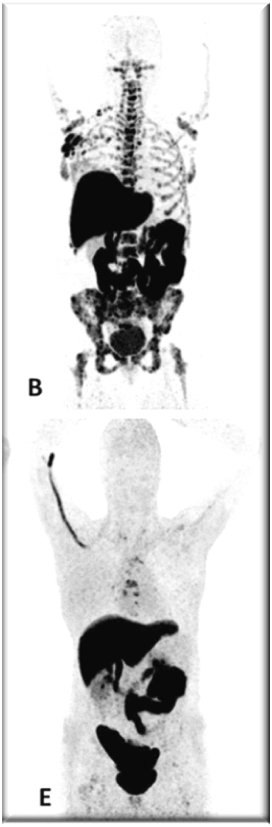

PET images of two patients with metastatic invasive lobular carcinoma responding (A-C) and not responding (D-F) to palbociclib + letrozole

Adapted with permission from Boers, J., et al. European Journal of Cancer. 2020; 126: 11-20

Upper row responder: (A) Baseline [18F]FDG-PET shows pathological uptake in axillary lymph nodes (right side) and in nearly all vertebrae and pelvic bones. (B) Baseline [18F]FES-PET with pathological ER expression in the axial skeleton (vertebrae, pelvic bones, proximal humeri and femora) and in axillar lymph nodes. (C) [18F]FDG-PET after 8 weeks shows almost complete metabolic response. The patient has been on treatment for more than 70 weeks.

Lower row non-responder: (D) Baseline [18F]FDG-PET shows pathological uptake in multiple skeletal lesions. (E) Baseline [18F]FES-PET with only some increased ER expression in thoracic vertebrae. (F) [18F]FDG-PET after 8 weeks shows no metabolic response, with some increase in the pathologic uptake in the multiple skeletal lesions.